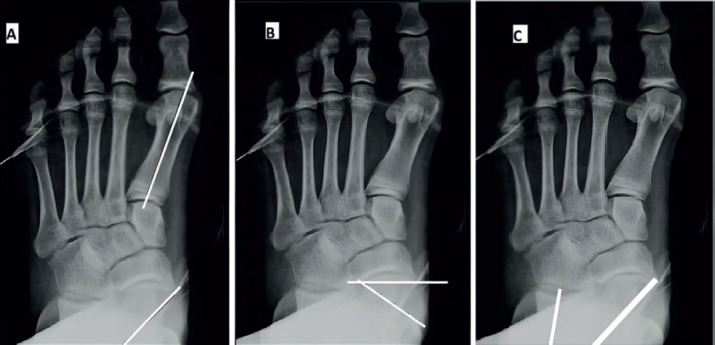

Methods: This is a prospective study and included 26 feet in 19 patients who underwent subtalar arthroereisis for symptomatic flexible flatfeet deformity. Preoperative and postoperative functional assessment based on the American Orthopedic Foot and Ankle Society (AOFAS) hindfoot scale. Radiographic parameters included preoperative and postoperative Kite`s angle, talonavicular coverage angle, Anterior-Posterior talo-1st metatarsal angle, Meary`s angle, talar declination angle, calcaneal inclination angle and lateral talocalcaneal angle.

Results: The mean follow-up period was 22.5±9.4 months and the mean preoperative AOFAS score was 54.6±6.0, while the mean AOFAS score at the last follow-up visit was 86.3±3.9 (P<0.001).The mean preoperative and postoperative radiological measurements were 19.0°±8.2° and 7.4°±3.9° for the AP Talo-1st metatarsal angle (P<0.001); 23.6°±9.1° and 8.0°±4.0° for talonavicular coverage angle (P<0.001); 35.4°±3.7° and 24.1°±3.4° for Kite`s angle (P<0.003); 22.4°±6.1° and 7.5°±3.7° for Meary`s angle (P<0.001); 41.0°±4.4° and 25.2°±7.1° for talar declination angle (P<0.001); 13.5°±3.7° and 21.3°±3.6° for calcaneal inclination angle (P<0.001) and 52.4°±7.2° and 42.9°±4.8° for lateral talocalcaneal angle (P<0.041) respectively.